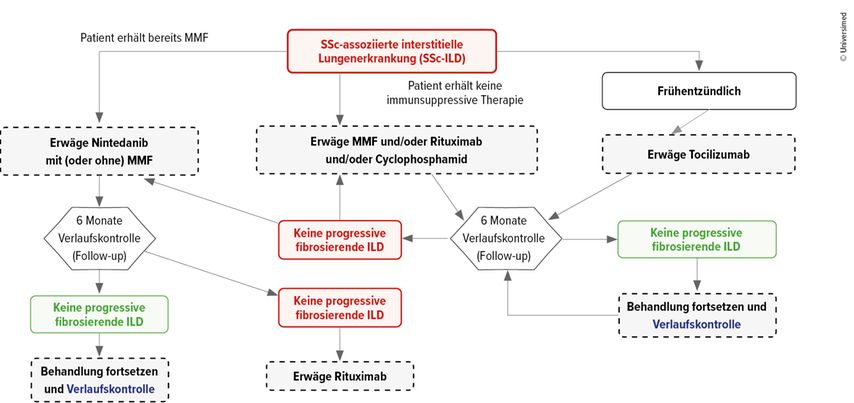

Besteht eine SSc-ILD, könne generell Nintedanib mit oder ohne Mycophenolat-Mofetil (MMF) gegeben werden, alternativ MMF und/oder Rituximab (RTX) und/oder Cyclophosphamid oder als dritte Option Tocilizumab. Letzteres insbesondere dann, wenn die Einschlusskriterien der entsprechenden Studie erfüllt seien, konkret falls eine frühe Erkrankung mit entzündlichem Phänotyp vorliegt (CRP erhöht, Arthritis, Myositis).13

Diskutiert werde eine Reevaluation bereits nach 3 statt nach 6 Monaten, da bereits dann eine Progression eintreten könne. Ist das der Fall, sollte das Präparat gewechselt oder – meist präferiert – ein weiteres potenziell synergistisches hinzugenommen werden. Bei stabiler Erkrankung solle die Therapie beibehalten werden.